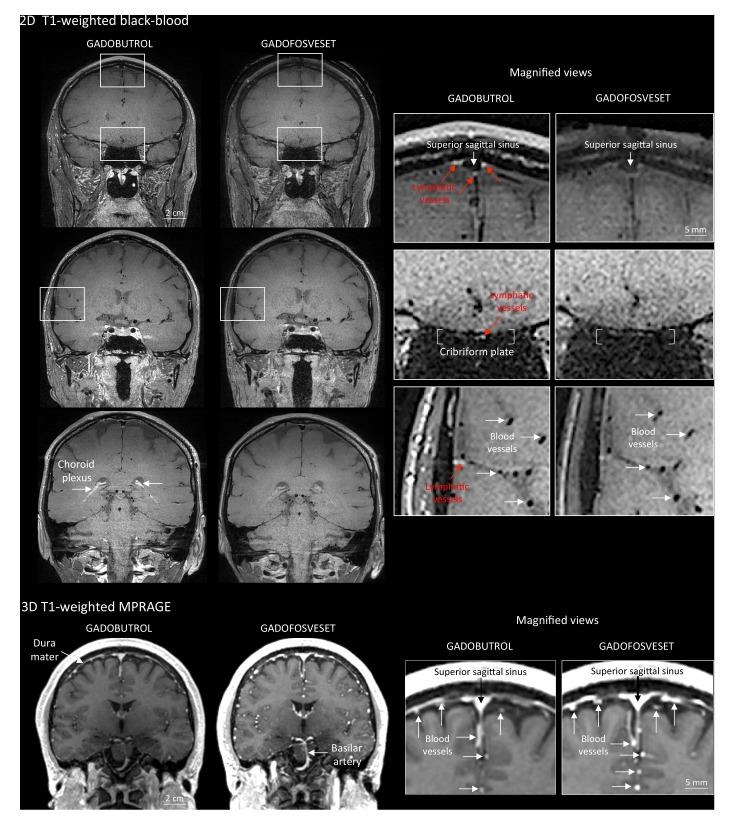

Here, we report the existence of meningeal lymphatic vessels in human and nonhuman primates (common marmoset monkeys) and the feasibility of noninvasively imaging and mapping them in vivo with high-resolution, clinical MRI. On T2-FLAIR and T1-weighted black-blood imaging, lymphatic vessels enhance with gadobutrol, a gadolinium-based contrast agent with high propensity to extravasate across a permeable capillary endothelial barrier, but not with gadofosveset, a blood-pool contrast agent. The topography of these vessels, running alongside dural venous sinuses, recapitulates the meningeal lymphatic system of rodents. In primates, meningeal lymphatics display a typical panel of lymphatic endothelial markers by immunohistochemistry. This discovery holds promise for better understanding the normal physiology of lymphatic drainage from the central nervous system and potential aberrations in neurological diseases.

在这里,我们报告了脑膜淋巴管在人类和非人类灵长类动物(普通狨猴)中的存在,以及使用高分辨率临床 MRI 对其进行非侵入性成像和体内绘图的可行性。在 T2-FLAIR 和 T1 加权黑血成像中,淋巴管增强与钆布醇增强,这是一种具有高倾向穿过可渗透的毛细血管内皮屏障外渗的基于钆的造影剂,但与血池造影剂钆氟塞特不同。这些与硬脑膜静脉窦并行运行的血管的拓扑结构再现了啮齿动物的脑膜淋巴系统。在灵长类动物中,脑膜淋巴管通过免疫组织化学显示出典型的一组淋巴管内皮标志物。这一发现有望更好地理解从中枢神经系统进行淋巴引流的正常生理学以及神经疾病中的潜在异常。